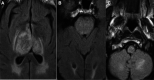

Figure 1.

A 65-year-old man with bithalamic edema from dural arteriovenous fistula (dAVF). A, An axial fluid attenuation inversion recovery (FLAIR) sequence showing expansile signal abnormality in the left greater than right thalamus, with prominent enhancement (B) and no restricted diffusion on the apparent diffusion coefficient (ADC) maps (C). D, An axial FLAIR sequence showing postbiopsy changes in the left thalamus (arrow), which showed reactive changes without evidence of malignancy. E, A time-of-flight magnetic resonance (MR) angiography which showed possible arterialized flow in the straight sinus. F, A lateral view digital subtraction angiography in the late arterialized phase, showing early venous drainage into the vein of Galen related to a dAVF (arrow).